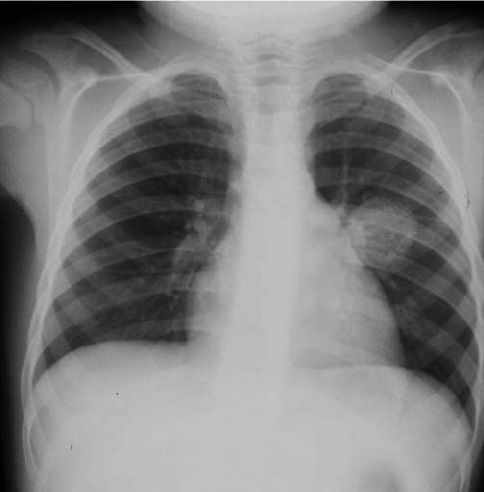

Radiological anatomy of a normal chest X-ray

Radiological anatomy of a chest X-ray

Checklist of areas to review on a chest X-ray

Key areas that should be reviewed on every CXR